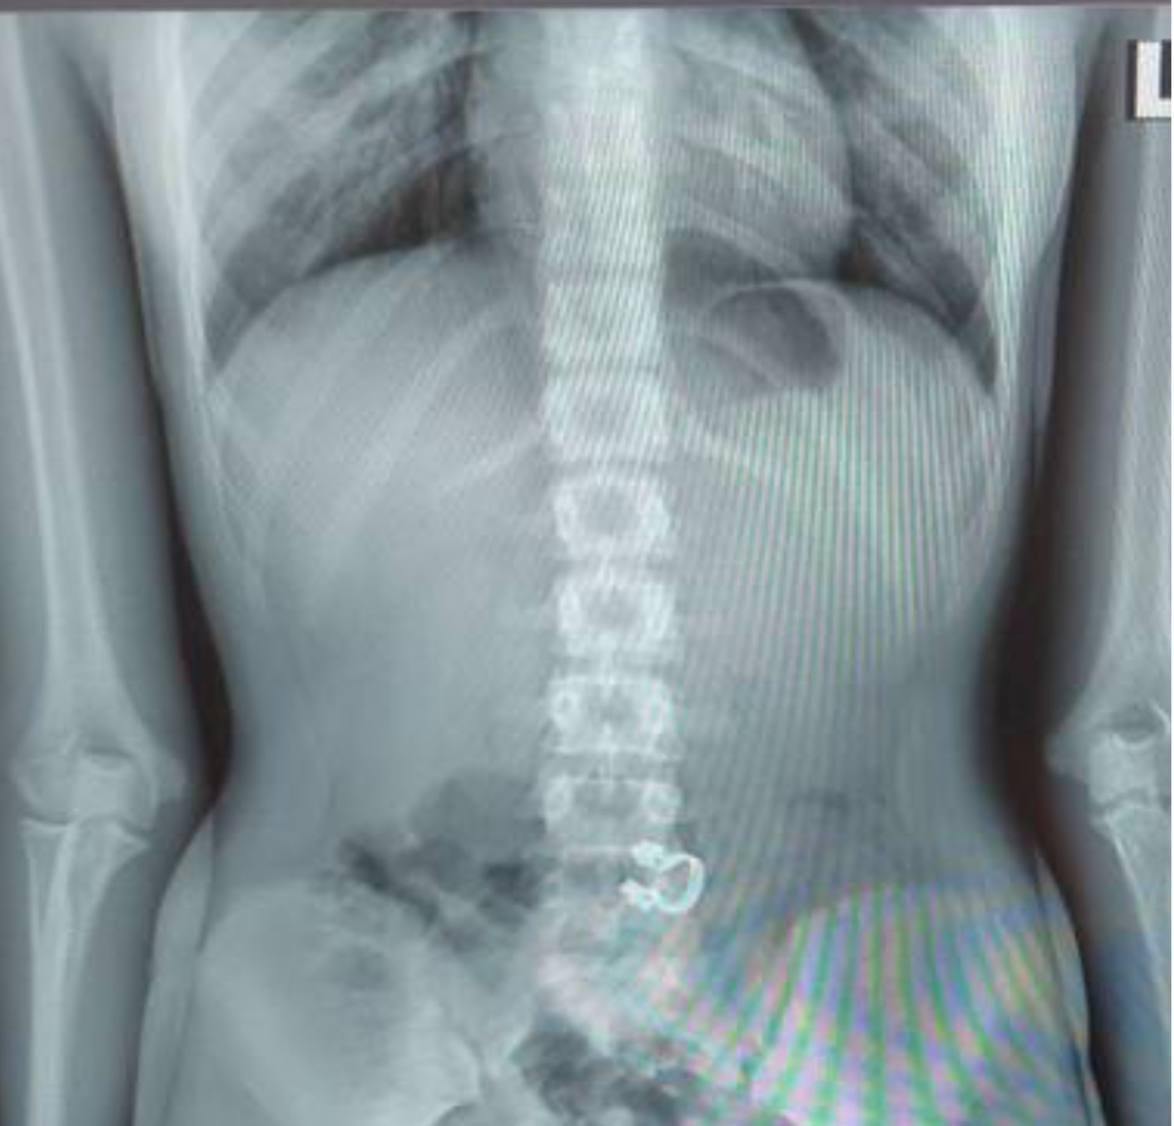

В Детский научно-клинический центр им. Л.М. Рошаля бригадой скорой помощи была экстренно доставлена 13-летняя девочка, которая случайно проглотила стоматологическую скобку. При поступлении врачи выполнили рентгенографию и госпитализировали пациентку в хирургическое отделение.

— Для извлечения инородного тела мы выполнили гастроскопию, в ходе которой захватили стоматологическую скобу эндоскопической петлей. Так как инородный предмет был острый, то это создавало высокие риски травмировать слизистую, мы поэтапно провели скобу через пищевод, устье пищевода и гортаноглотку. Процедура длилась около 10 минут и прошла успешно. При контрольном осмотре травматических дефектов слизистой не определялось, — сказала врач-эндоскопист Анастасия Лазарева.